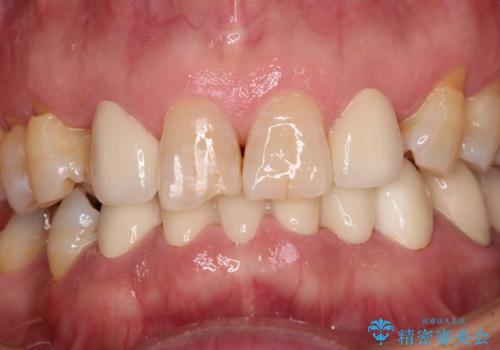

- 強い咬み合わせと前歯のデコボコを気にして来院された患者様です。

下顎前歯が全て隠れてしまうほどの深い咬合で、左右の奥歯は1歯対1歯で咬み合う状態でした。

前方に移動している上顎臼歯を補助装置にて遠心移動させることで1歯対2歯の臼歯咬合を目指し、同時に深い咬合を改善していくこととしました。